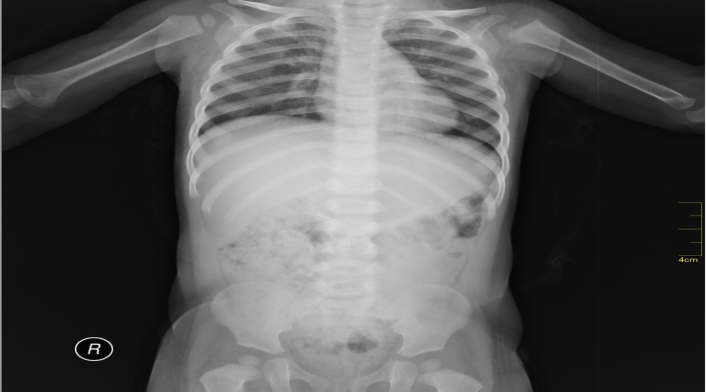

También conocida como la enfermedad de los huesos de cristal es un trastorno que se caracteriza por el gran debilitamiento de todos los huesos del cuerpo. Es considerada como una enfermedad genética y crónica a la cual no se le ha encontrado una cura definitiva.

Igualmente puede causar músculos débiles, dientes quebradizos, una columna desviada y pérdida del sentido del oído. La enfermedad de los huesos de cristal es causa por un defecto en el gen que produce colágeno para el cuerpo.